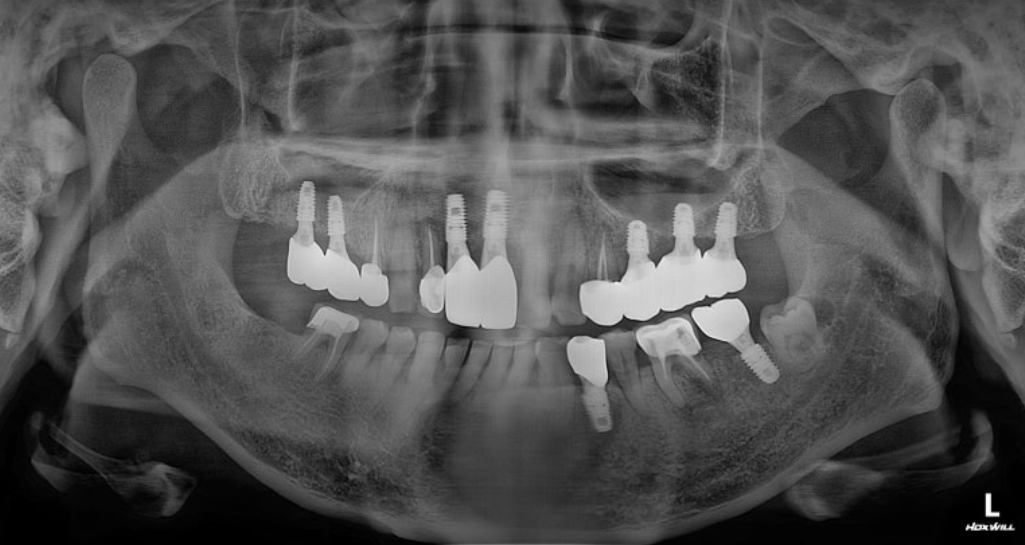

사진상 위턱 앞니 부위에 매우 큰 낭종이 보입니다. 환자분께선 매우 큰 통증을 호소하셨습니다.

3차원 CT 영상 소견입니다. 구강내 기준으로 오른쪽 앞니 상방으로 과잉치아가 보이며, 과잉치아 주변에 매우 큰 낭종이 있습니다. 인접한 다른 치아의 입천장쪽으로도 과잉치가 매복되어 있으며, 다행히 해당치아는 낭종을 형성하지는 않았던 상태입니다. 촬영일시 : 2024.05.02. 정면 ct 사진입니다. 코 아래쪽으로 2개의 과잉치아가 매복되어 있으며 매우 큰 낭종도 보입니다. 2개의 매복과잉치와 코 아래의 낭종을 동시에 제거하는 수술과 동시에, 왼쪽 아래턱에 심하게 충치가 진행된 치아를 발치하고 임플란트를 식립하는 수술까지 진행했으며 수술시간은 총 36분에 걸쳐서 순조롭게 진행되었습니다 ㅎㅎ 촬영일시 : 2024.05.02. 과잉치 발치와 낭종 적출술을 동시에 진행하고 있는 모습이며, 가장 오른쪽 사진은 적출된 낭종과 과잉치입니다. 낭종과 심하게 진행된 치주염으로 인해 앞니 두개 치아는 발치를 해야하는 상황이었으며, 낭종 제거 후 6개월 이상 기다렸다가 뼈의 회복이 진행되면 임플란트 식립을 하기로 했습니다 ㅎㅎ 촬영일시 : 2024.12.10. 아래쪽 임플란트 수술까지 합쳐서 총 36분에 걸쳐서 순조롭게 진행되었으며, 환자분께서도 만족하셨던 증례입니다. 촬영일시 : 2025.02.14. 대략 6개월 후 보철까지 모두 완료된 엑스레이 사진입니다. 아무리 복잡하고 어려운 치료라도 자신있습니다. ㅎㅎ 부담갖지 마시고 내원해주시면 최선을 다해 치료하겠습니다. 오늘은 도화동치과 365서울앞선치과에서 매복된 과잉치와 그로인해 생긴 낭종을 제거한 증례를 소개해드렸습니다. 앞으로도 좋은 치료 증례로 찾아뵙겠습니다 ! [ 치료기간: 2024년 5월2일 ~ 2025년 2월 14일 ] ※ 365서울앞선치과의원의 모든 포스팅은 각 진료과 의료진이 직접 작성합니다. 365서울앞선치과의원 블로그의 임상 케이스 게시물은 환자분께 의학적으로 정확하고 상세한 정보를 드리기 위해 각 진료과 의료진이 직접 작성하며, 모든 증례 사진은 본원 의료진이 직접 시술한 증례를 촬영한 것으로, 의료법 제23조, 제56조에 의거하며 환자분의 동의를 얻어 포스팅에 사용하였습니다. 또한 해당 케이스는 본 환자분의 치료 결과이며, 환자 상태에 따라 치료의 결과는 달라질 수 있습니다. |